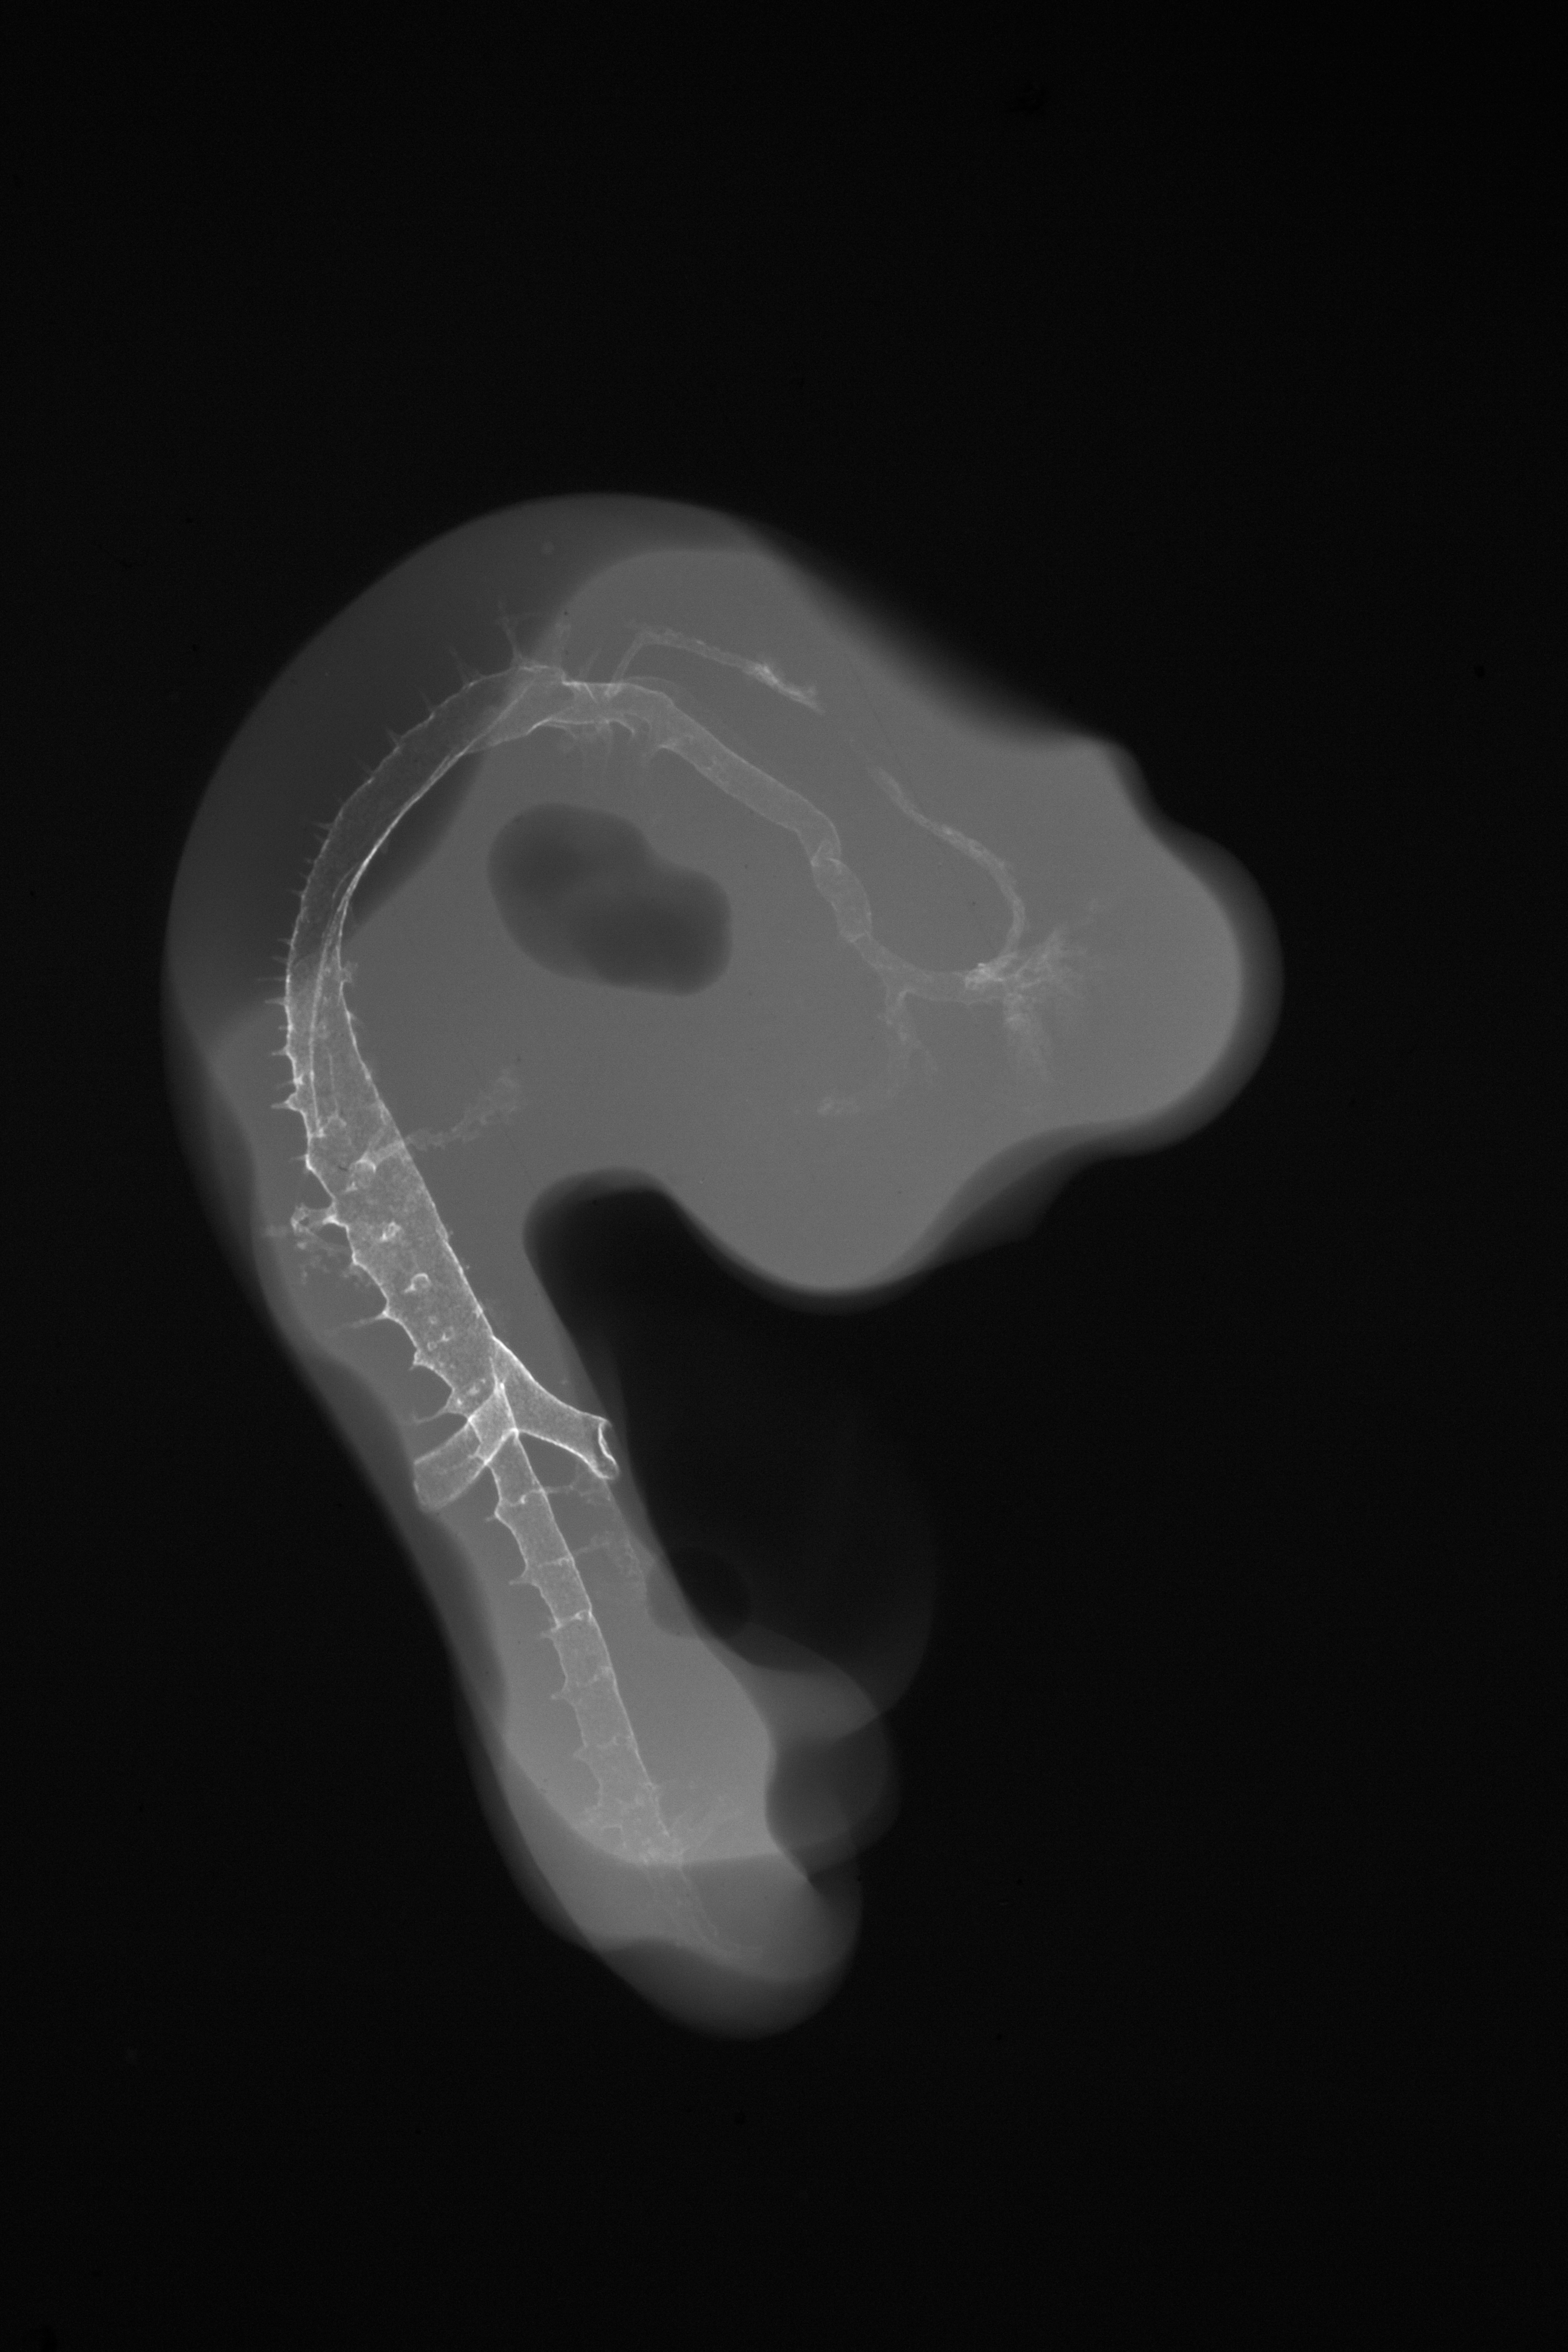

Chick Embryo Microangiography

Hamburger-Hamilton (HH) Stage 23 (approx. 4 days)

X-Ray Micrographs

Drawing